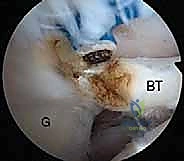

| الأساليب المستخدمة | العلاج الطبيعي، مسكنات الألم، حقن الكورتيزون أو البلازما (PRP). | خياطة الوتر وإعادته لمكانه باستخدام المناظير ومثبتات خطافية. |

2. إحداث الثقوب (Portals) واستكشاف المفصل

يقوم الدكتور هطيف بعمل 3 إلى 4 ثقوب صغيرة جداً حول الكتف. يُدخل كاميرا المنظار (Arthroscope) لعمل جولة استكشافية شاملة لداخل المفصل، وتقييم الغضاريف، أوتار الكفة المد